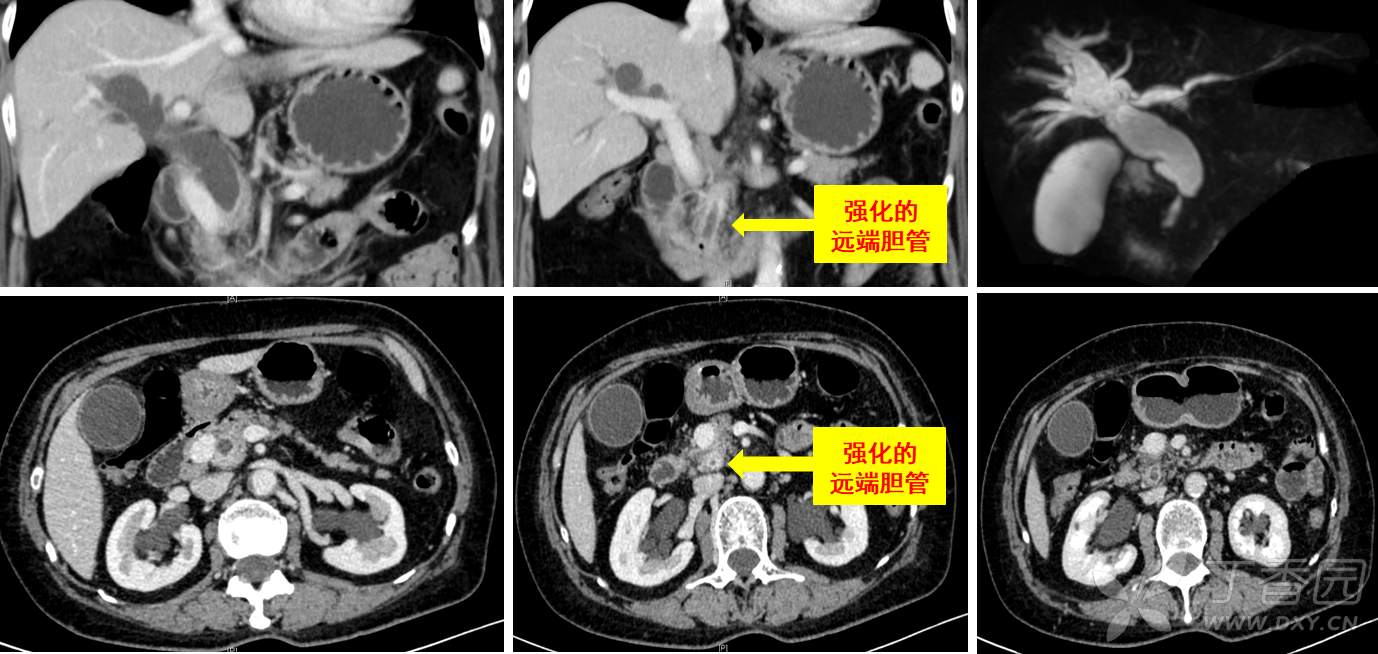

影像检查如下图,胆管下端狭窄并强化;动脉和门脉没有问题;结合CA19-9进行性升高,手术指征是有的。有了前述的两怪,如果给您,干不干?(看完故事前,仔细看看下面的片子,第三怪就隐藏其中)

手术开始进展顺利,离断十二指肠后蒙了,因为门静脉前方没有胰腺!(如下图)难道是胰颈菲薄,和幽门一块断了?术中再次阅片,发现胰头确实从门脉后方进入了十二指肠。读到这,各位可以再次仔细看术前CT,门静脉处在十二指肠降部和胰头之间!3D重建可以更直观的展现该患者的第三怪。